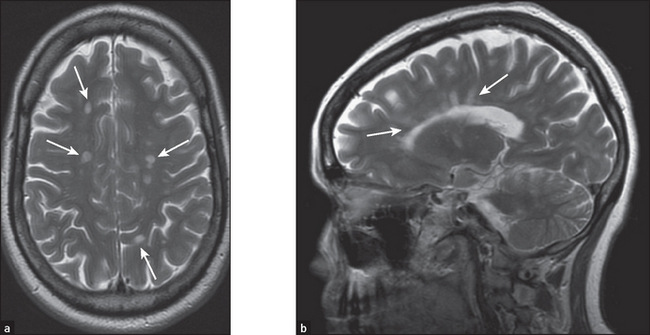

Some common examples of important diagnostic scans are shown in Figures 36.2–36.8 and 36.10.

Figure 36.4 Multiple sclerosis The lesions of multiple sclerosis on MRI tend to involve the periventricular area, the corpus callosum and the optic nerves (solid white arrows). (a) The lesions produce discrete, globular foci of high-signal intensity (white) on T2-weighted MRI scans. (b) Ovoid lesions with their long axis perpendicular to the ventricular surface are called Dawson’s fingers (solid white arrows). (Herring W. Learning radiology: recognising the basics, 2dn edn. Saunders, 2011.)